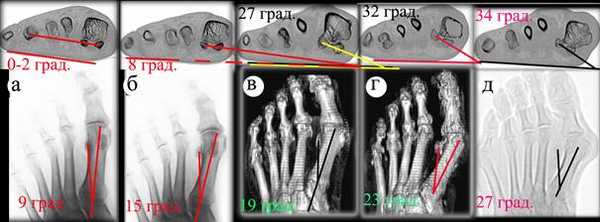

Методом сравнения СГУ и M1SS на серии СКТ и снимков в прямой проекции аналогичных стоп того же пациента в прямой проекции нами установлена зависимость показателей углов у пациентов с разными степенями поперечного плоскостопия (рисунок 3).

Рис. 3 а-д - стопы пациентов с различной степенью плоскостопия. Верхний ряд - СКТ на уровне сесамовидных костей (без нагрузки) и показаны углы СГУ. Нижний ряд - снимки в прямой проекции переднего отдела стоп (без нагрузки), на которых получены M1SS углы

На рисунке 3а у пациента, не имеющего поперечного плоскостопия или имеющего крайне незначительную степень ротации (т.к. на прямой рентгенограмме наружный край латеральной сесамовидной кости выступает за край плюсневой кости), СГУ стопы (на СКТ) не превышает 1-2 градусов: линия, проведенная через центры сесамовидных костей практически параллельна горизонтальной линии, угол M1SS равен при этом примерно 9 градусам. На рисунках 3 б-д с увеличением СГУ соответственно увеличивается и угол M1SS. На основании полученных данных, мы обнаружили прецизионную корреляцию между углом ротации сесамовидных костей на СКТ и углом вывихивания латеральной сесамовидной кости (в первый межпальцевой промежуток), полученным по прямой рентгенограмме. В каждом замере угол M1SS, определенный на прямой проекции рентгенограммы, меньше СГУ приблизительно на 8 градусов.